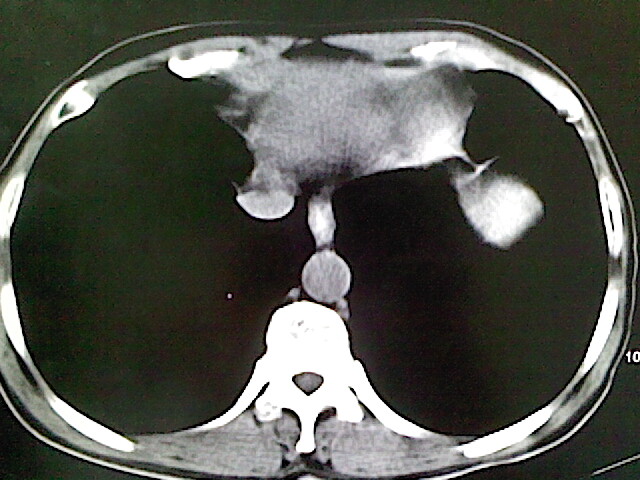

标题: CT18630:男,54岁,乙肝,大家看怎么样? [打印本页]

男,54岁,乙肝,大家看怎么样?

肝脏的要有增强敢说话

强化再讨论